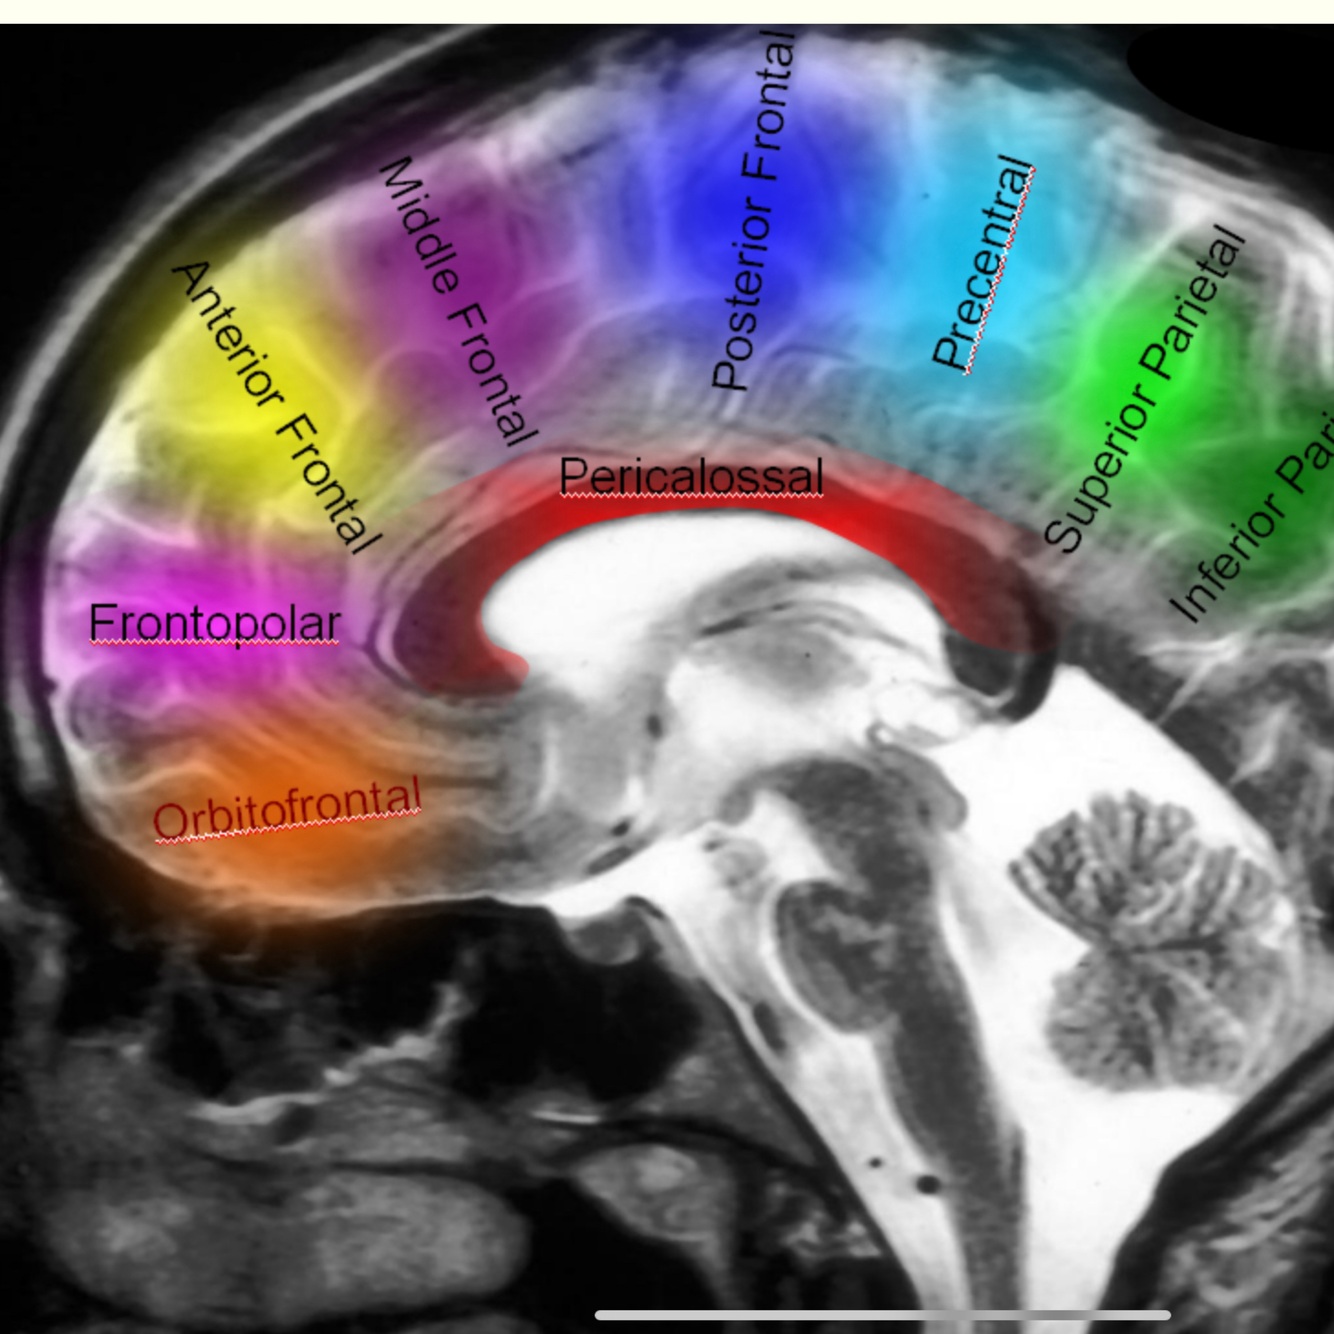

A 1 pre communicating»_space; end ACOM

A2 post communicating > terminate rousting genum junction of corpus collosum

A3 peri collosal > end anterio genum

A4 supra collosal above the body of corpus collosum , anterior Cornoal suture

A5 post collosal terminal end above body of corpus collosum posterior to Cronal suture

Frontopolar

2nd cortical branch

Supply medical frontal pole

Collos marginal

Branches anterio internal frontal ( anterior , middle , posterior )

Paracentral

Preicollosal A5

Superior to genum

Superior internal partial A

Inferior internal partial precuneat A